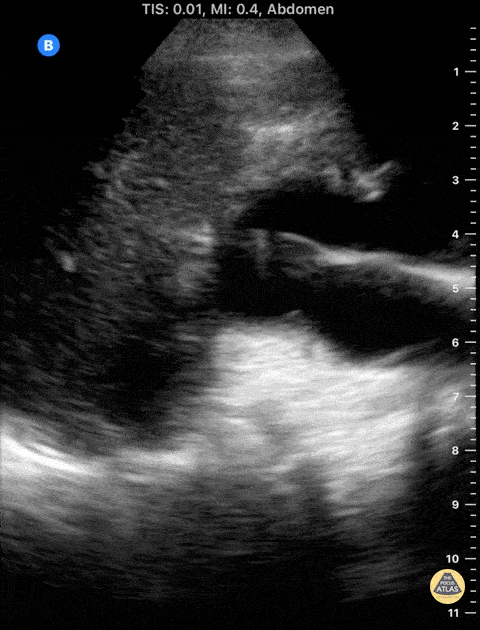

88 y/o female presents with three days abdominal pain, distension, vomiting and worsening on renal function. Hx of previous ovarian cancer with right ureteral stricture (estenosis). Ureteral stent in 2020, recently changed 2 weeks ago. No fever, and currently passing urine without issues. POCUS shows severe HUN to the right. Notice the anatomical distortion of the calyceal collecting system as well as thinning of the renal cortex. Dr Felipe Urriola Perez Resuscitation Fellow The Royal London Hospital ED